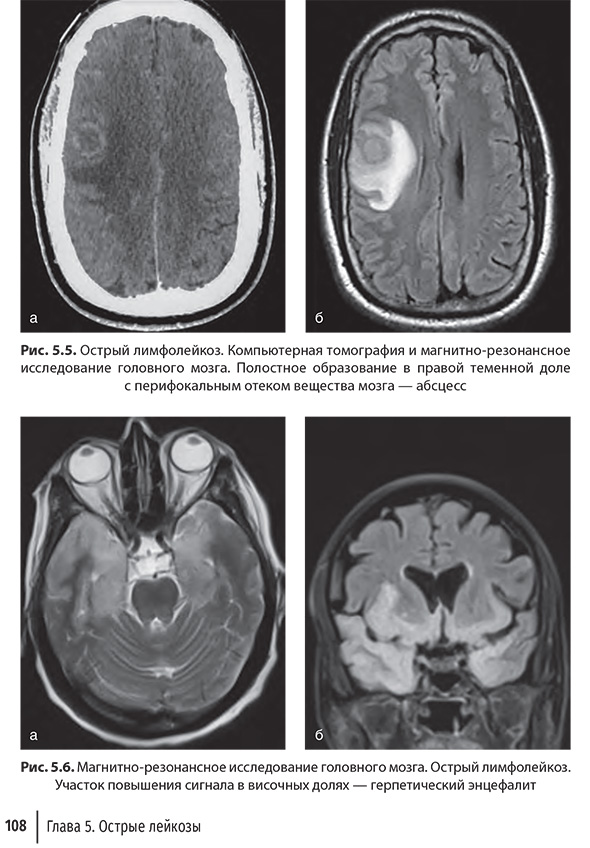

Глава 5. Острые лейкозы

и лечении острых лейкозов